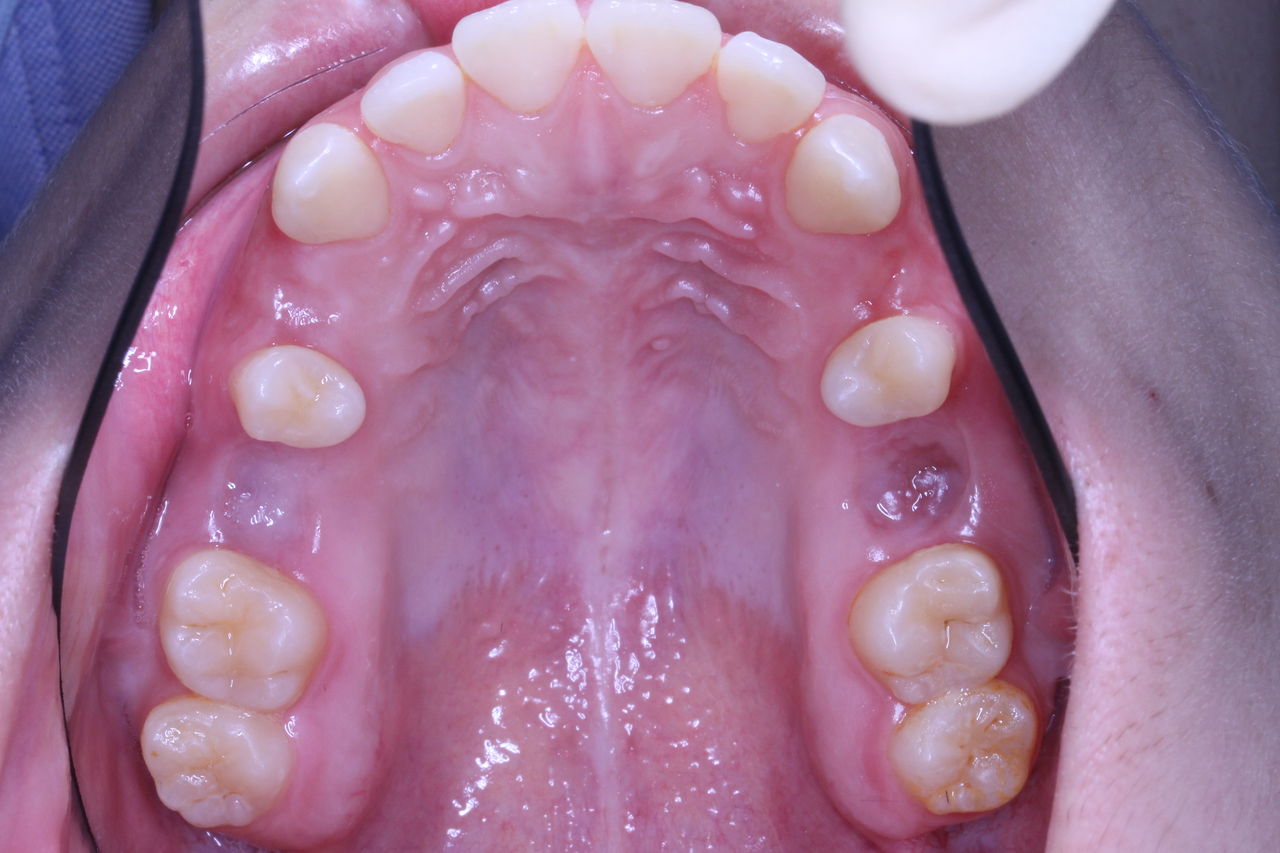

たとえばこのような状況の場合、犬歯はまったく機能しておりません。

これを抜歯して矯正治療をおこない、他の歯を100%機能させております。

たまたま、他の医院で矯正診断をして抜歯したまま放置してしまった患者さんが来院されました。

本人は1年くらい放置といっておりますが、僕の予想ではそんな期間でなないと思います。

この状況はかなり深刻です。

上下のかみ合わせも大変な状況です。

また、場合によっては他医院にいっても治療を断られてしまうと(つまり治療不可能)といわれてしまう可能性も高いです。正直、私も通算2000症例近く診断をしてきましたが、この状況ははじめての経験でした。

このように抜歯したまま放置しておくと向かい側の歯がのびてきてしまいます。

よくみればわかりますが、歯茎と歯がかみあってます。

正面からみると、普通のガタガタな歯並びですが、機能的には大変な状況です。

こんな具合です。

さきほどの患者さんの治療経過です。